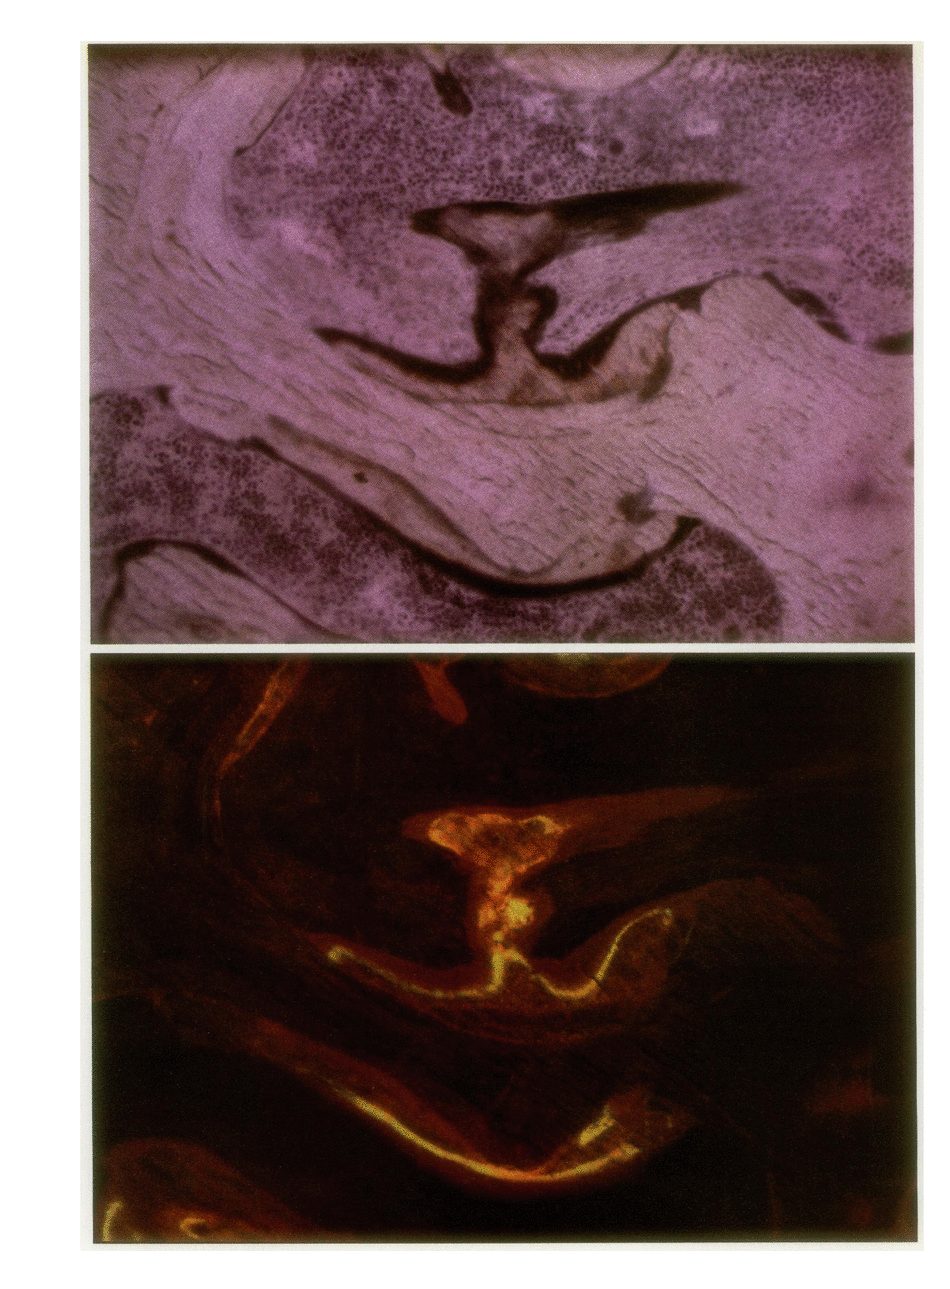

To define the primary effects of aluminum on bone in the mammalian species, we examined the dose/time-dependent actions of aluminum in normal beagles. Administration of low dose aluminum (0.75 mg/kg) significantly elevated the serum aluminum (151.7 +/- 19.9 micrograms/liter) compared with that in controls (4.2 +/- 1.35 micrograms/liter) but did not alter the calcium, creatinine, or parathyroid hormone. After 8 wk of therapy, bone biopsies displayed reduced bone resorption (2.6 +/- 0.63 vs. 4.5 +/- 0.39%) and osteoblast covered bone surfaces (2.02 +/- 0.51 vs. 7.64 +/- 1.86%), which was indicative of low turnover. In contrast, prolonged treatment resulted in increased bone volume and trabecular number (38.9 +/- 1.35 vs. 25.2 +/- 2.56% and 3.56 +/- 0.23 vs. 2.88 +/- 0.11/mm) which was consistent with uncoupled bone formation. Administration of higher doses of aluminum (1.20 mg/kg) increased the serum aluminum further (1242.3 +/- 259.8 micrograms/liter) but did not affect calcium, creatinine, or parathyroid hormone. However, after 8 wk of treatment, bone biopsies displayed changes similar to those after long-term, low-dose therapy. In this regard, an increased trabecular number (3.41 +/- 0.18/mm) and bone volume (36.5 +/- 2.38%) again provided evidence of uncoupled bone formation. In contrast, in this instance poorly mineralized woven bone contributed to the enhanced bone volume. High-dose treatment for 16 wk further enhanced bone volume (50.4 +/- 4.61%) and trabecular number (3.90 +/- 0.5/mm). These observations illustrate that aluminum may stimulate uncoupled bone formation and induce a positive bone balance. This enhancement of bone histogenesis contrasts with the effects of pharmacologic agents that alter the function of existing bone remodeling units.